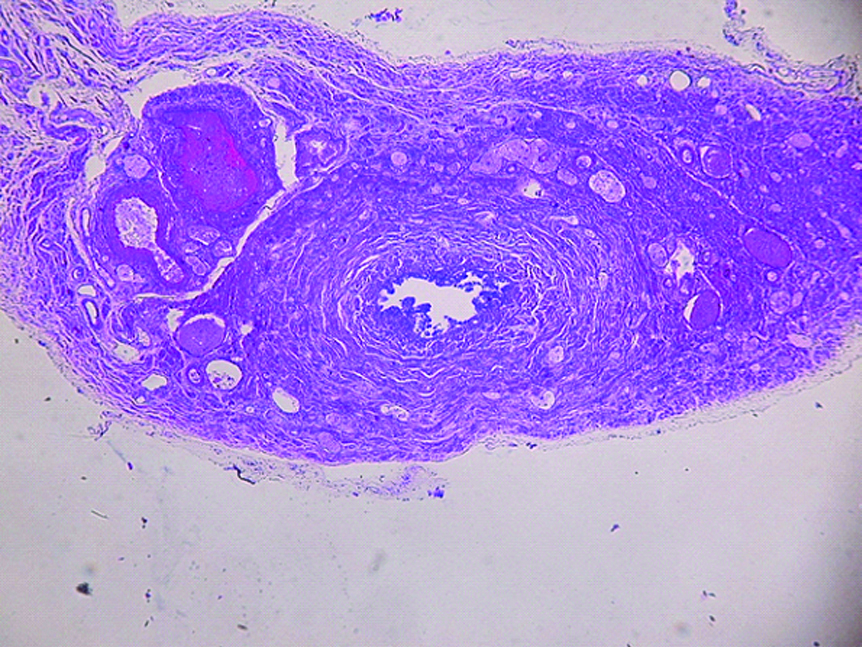

При исследовании гистологических препаратов перешейка маточных труб определили, что его слизистая оболочка образована однослойным столбчатым эпителием, а также собственной пластинкой, сформированной рыхлой соединительной тканью. Ею выполнены также и множественные продольные складки, характерные именно для маточных труб (рисунок 1).

Рисунок 1. Фрагмент перешейка маточной трубы женщины в возрасте 25 лет. Окраска гематоксилином и эозином. ×10.

Figure 1. A fragment of the isthmus of the fallopian tube of a woman aged 25 years. Staining with hematoxylin and eosin.10x.